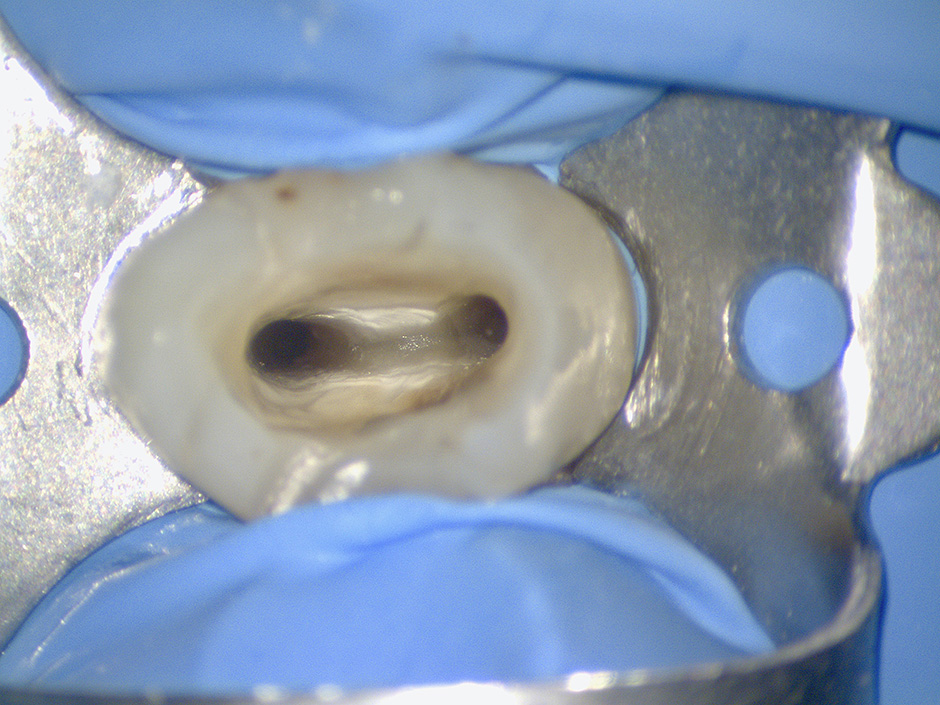

Nei casi complessi di calcificazione camerale e canalare, ad esempio, solo con un adeguato sistema di ingrandimento e di illuminazione è possibile distinguere il materiale calcifico dai tessuti normali e reperire le più piccole tracce della posizione degli orifizi canalari.